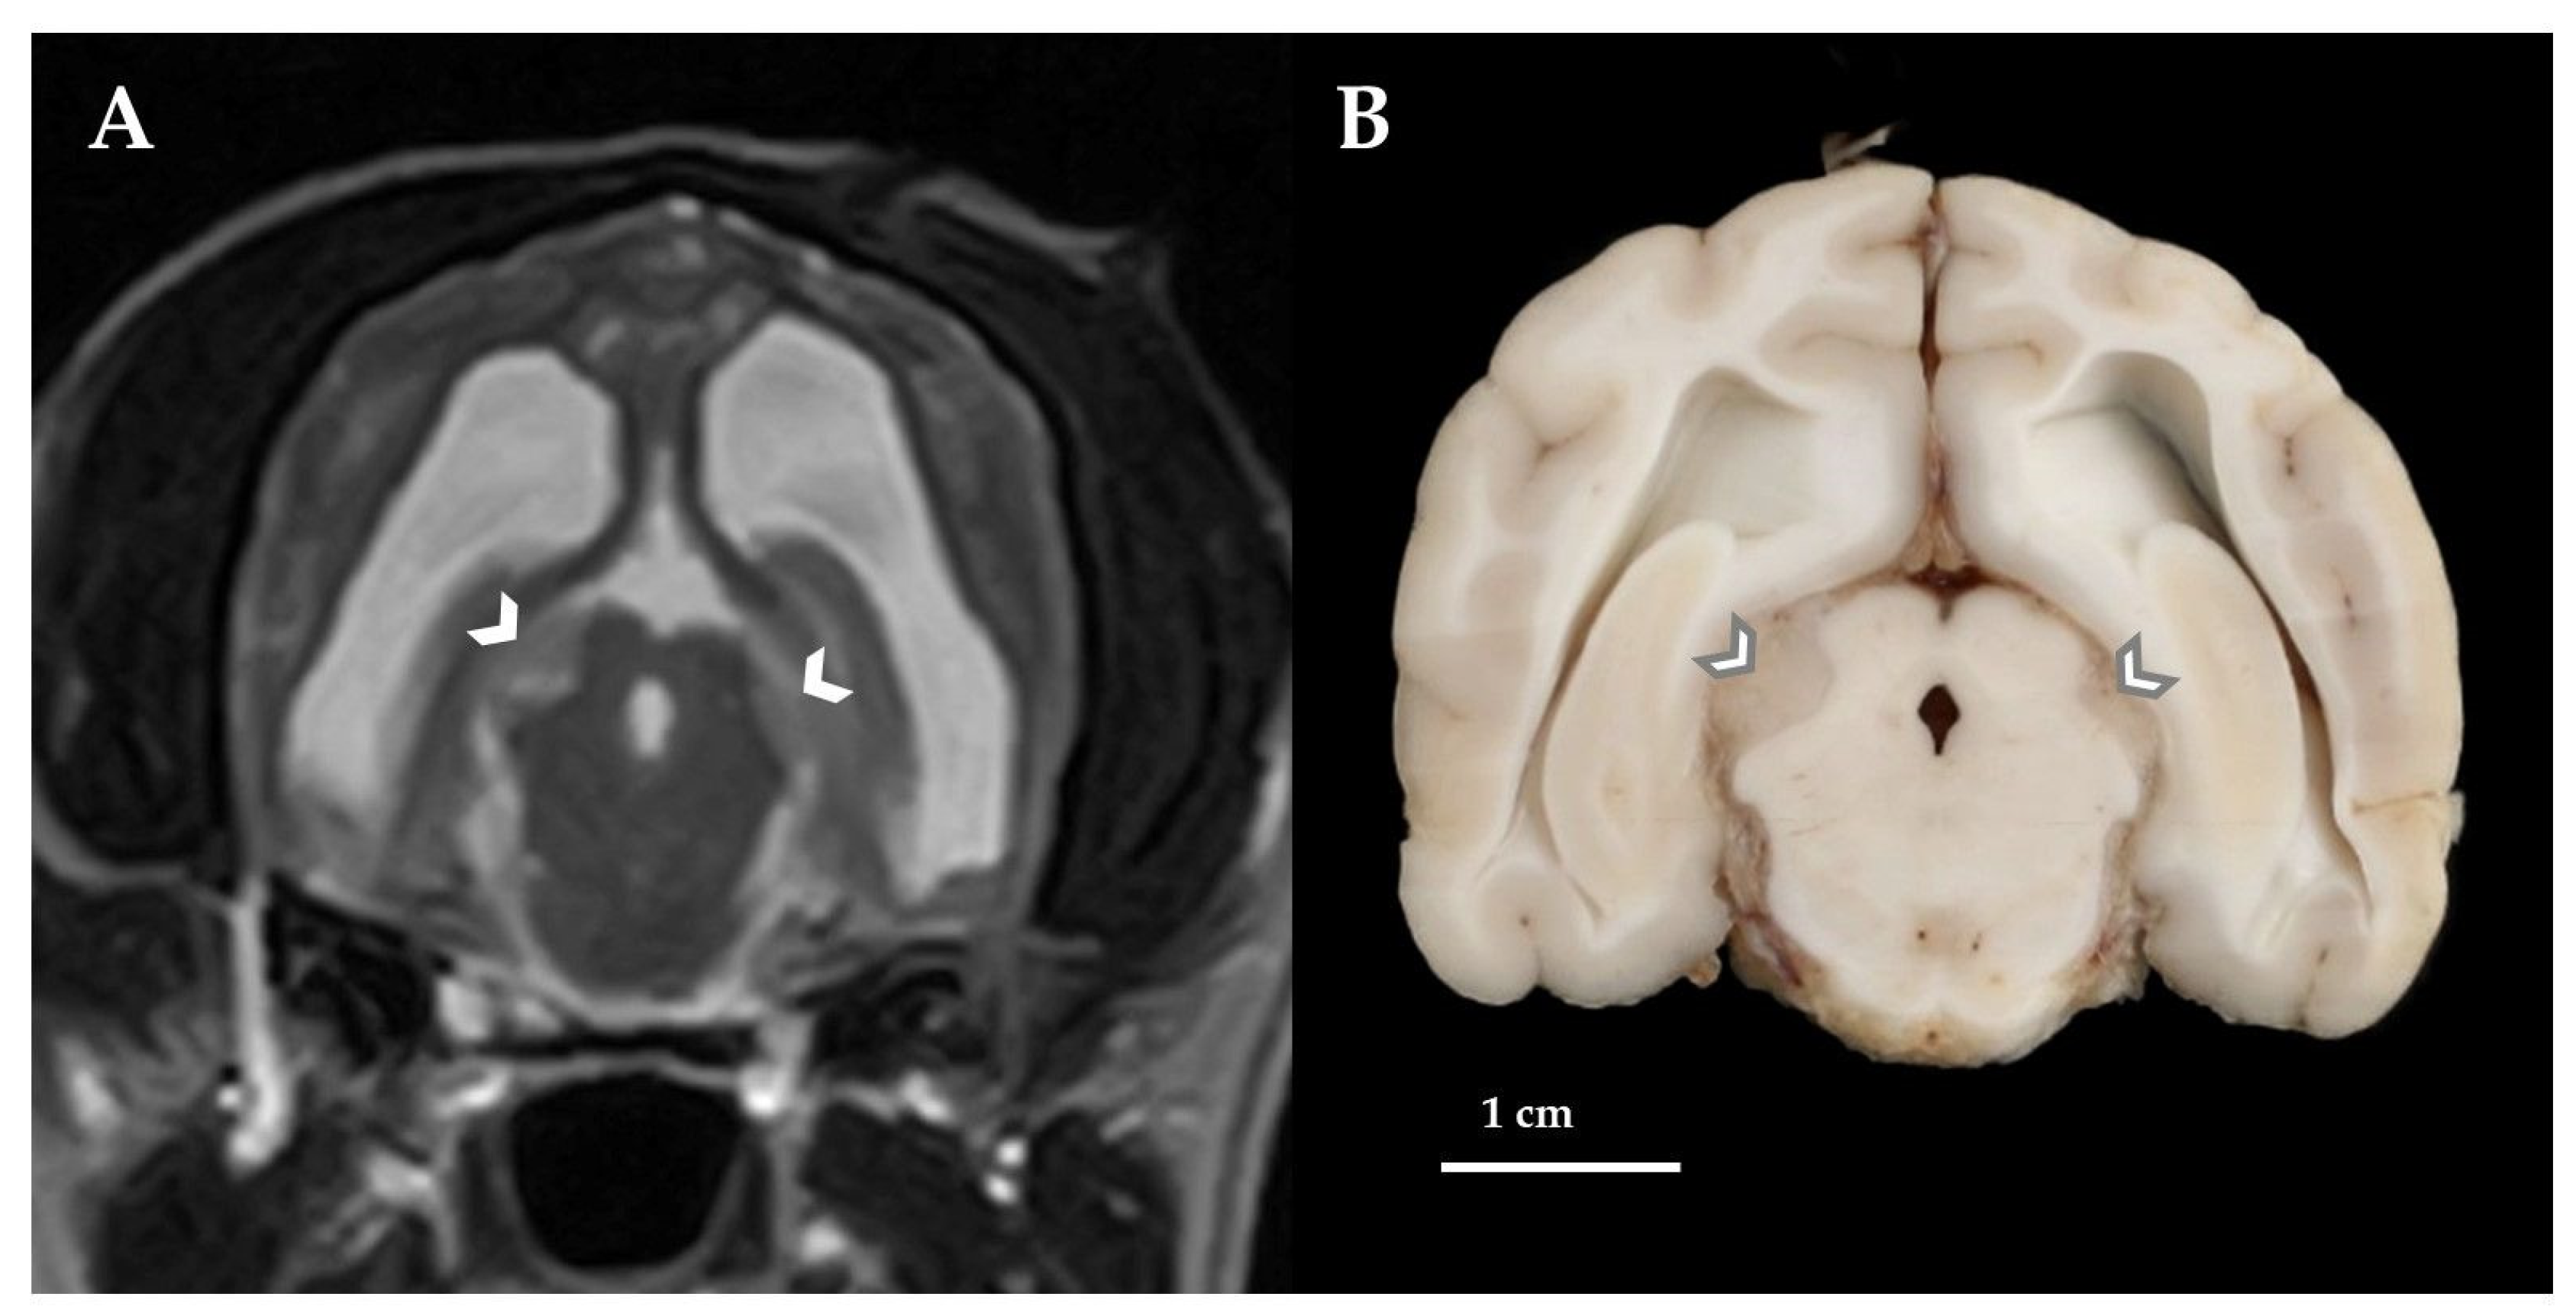

2. Case Presentation